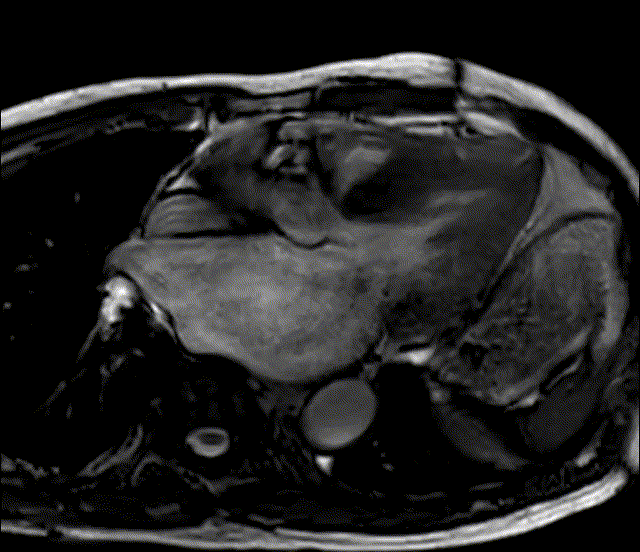

下午的第一台手术依然是来自复旦大学附属中山医院的王春生教授团队。该病例为42岁男性,心脏超声提示:先天性主动脉瓣二叶式畸形伴重度返流,主动脉窦部及升主动脉增宽,EF:59%,主动脉瓣环前后径:30mm,主动脉窦部:42mm,升主动脉:40mm。综合考虑年轻患者对微创瓣膜修复的渴望及主动脉瓣病变特点,王春生教授决定经微创入路对患者主动脉瓣实施三维解剖修复手术。

手术采用第3肋间胸骨上段切口,行中心体外循环插管。手术采用王春生教授首创的三维解剖修复技术:横断主动脉后,充分游离主动脉根部及左右冠脉开口,将人造血管固定在主动脉瓣基底环水平。再对病变瓣叶进行修复,通过修剪假嵴和瓣叶中心性折叠等技术恢复畸形瓣叶的对称结构。术中同期将扩张菲薄的近端升主动脉管壁行人造血管替换,避免远期潜在的主动脉瘤/夹层可能。术后食道心超提示未见明显主动脉瓣反流,瓣叶启闭正常,最大和平均跨瓣压差仅为8mmHg和4mmHg。术后主动脉瓣环前后径25mm,窦部直径28mm。